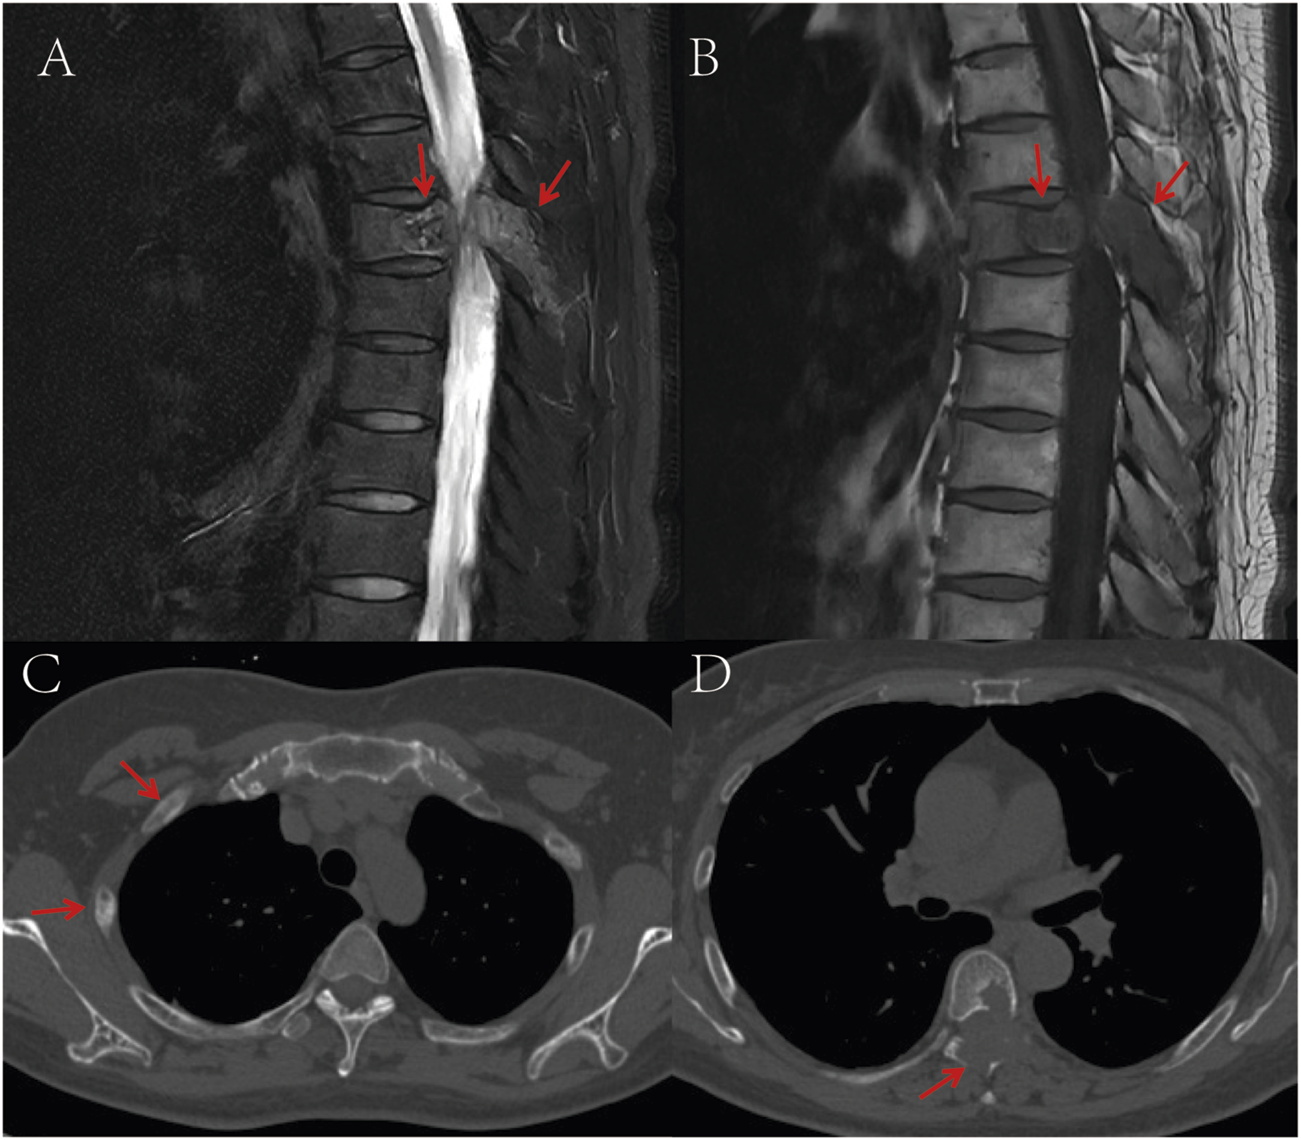

A 53-year-old female presented with persistent back pain for 3 months and was admitted on 8 March, 2022. Magnetic resonance imaging (MRI) (Figures 1A,B) revealed a neoplastic lesion in the left posterior aspect of the T6 vertebral body and adjacent paravertebral regions, involving the left 5th–7th costovertebral joints, the inferior edge of the T5 spinous process, and the left T6 vertebral appendages. Chest computed tomography (CT) (Figures 1C,D) further demonstrated osteoblastic bone destruction in the left 1st–2nd ribs and right 2nd–4th and 11th ribs, along with osteolytic destruction of the T6 vertebral body and appendages accompanied by soft tissue mass formation and scattered tumor bone formation. A percutaneous biopsy of the thoracic lesion (Figures 2A,B) revealed spindle cells and small round cells with moderate atypia and focal osteoid formation. Immunohistochemistry showed Vimentin (+) and SATB2 (+), confirming the diagnosis of osteosarcoma. Based on imaging and histopathological findings, the patient was diagnosed with stage IV thoracic osteosarcoma (cT1N0M1, AJCC 8th edition).

FIGURE 1

(A) T2-weighted MRI shows a space-occupying lesion in the T6 vertebral body and adjacent structures, demonstrating high signal intensity; (B) T1-weighted MRI reveals the same T6 vertebral body lesion with low signal intensity; (C) CT bone window imaging demonstrates osteoblastic bone destruction in bilateral ribs, suggestive of multiple metastatic lesions; (D) Non-contrast CT bone window imaging displays destruction of the T6 vertebral body and adjacent structures accompanied by a soft tissue mass, with punctate and flaky neoplastic bone formation within the lesion. The red arrows in the images indicate the location of the tumor.